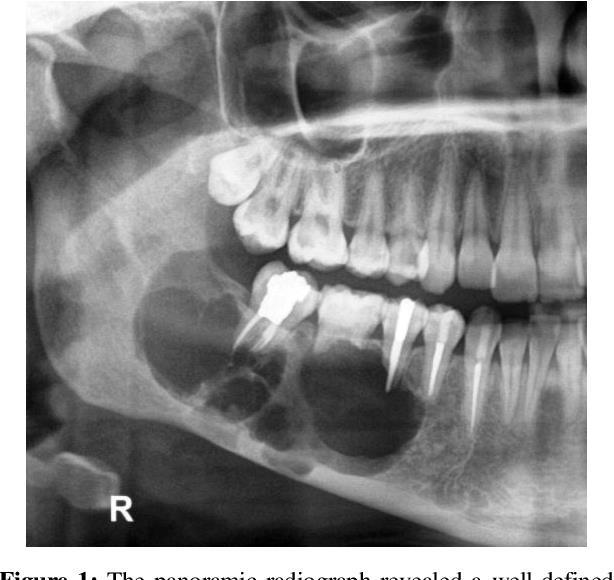

38-year-old Female, Cyst Associated With Unerupted Wisdom Tooth.

??

Case 9 Diagnosis

Odontogenic keratocyst

Salient points •Basal cell palisading •Corrugated parakeratosis •Focal inflammation –loss of above and “non-specific” features •Consistent loss of PTCH tumour suppressor gene- GorlinGoltz syndrome •Tendency for recurrence